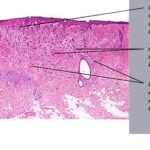

Morpheaform Basal Cell Carcinoma

Morpheaform or infiltrative BCC consists of strands of tumor cells embedded within a dense fibrous stroma . Tumor cells are closely packed and, in some cases, only one cell thick. Strands of tumor extend deeply into the dermis. The cancer is often larger than the clinical appearance indicates. Recurrent BCC may also demonstrate infiltrating bands and nests of cancer cells embedded within the fibrous stroma of scar.